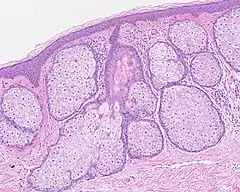

Les glandes sébacés ont une architecture acinaire (comme une grappe de raisin) et n'ont pas de lumières propre. Elles sont composés de sébocytes matures, dont la sécrétion est le résultat de leur mort par apoptose, ce qui revient à une sécrétion holocrine. Le remplacement des cellules est assuré par les cellules de la matrice reposant sur la membrane basale[5].L'annexe pilo-sébacée constituée du follicule pileux, des glandes sébacés et des muscles arrecteurs du poils, résulte d'une invagination épithéliale[4].

Annexe pilosébacée avec glandes sébacés s'abouchant à un follicule pileux.

Multiples glandes sébacés s'abouchant à un follicule pileux.